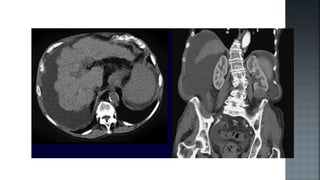

 Permite establecer el diagnostico con certeza.

 Puede ser realizada por vía percutánea o laparoscópica.